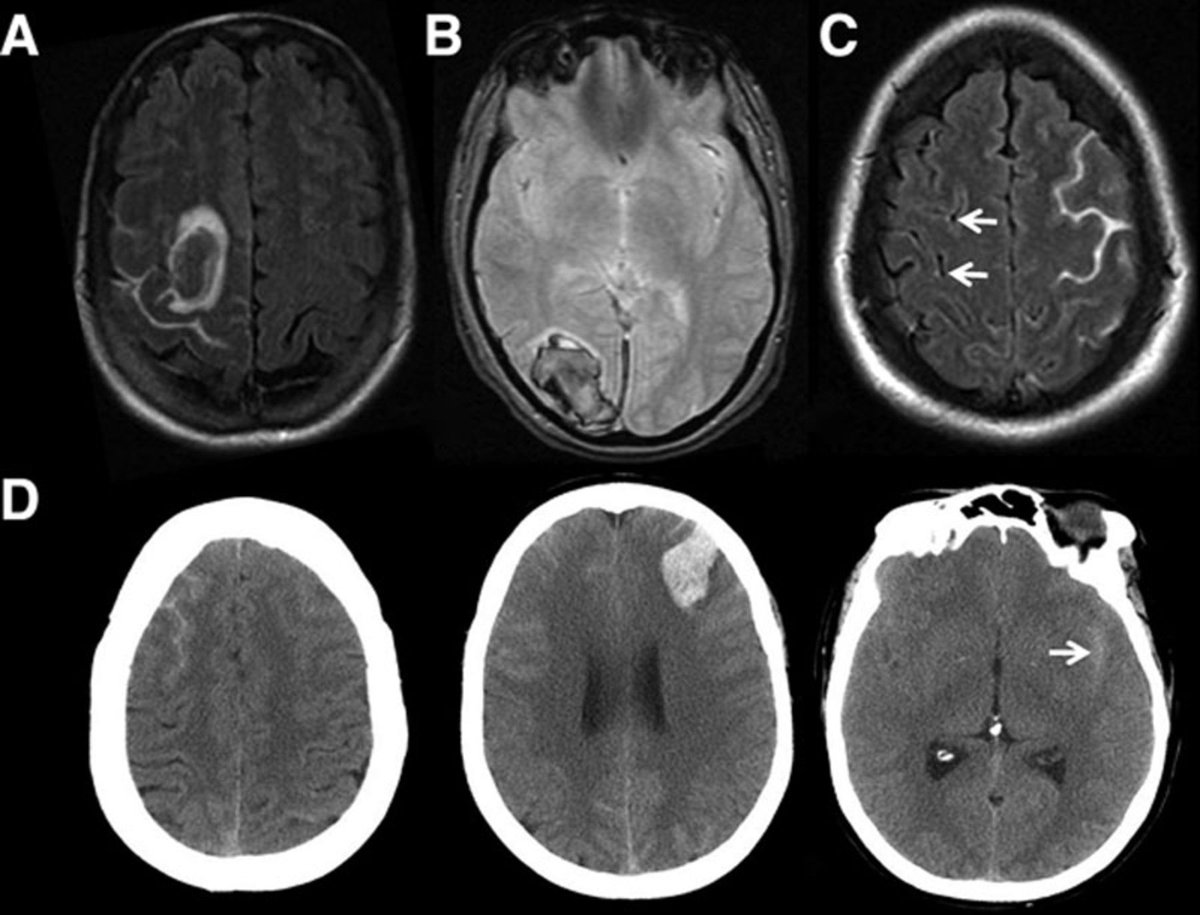

血管攣縮像を経時的に捉えた典型的可逆性脳血管攣縮症候群の1例 Serial Imaging Of Reversible Cerebral Vasoconstriction Syndrome A Case Report Soh Sampei 16 Nihon Kyukyu Igakukai Zasshi Journal Of Japanese Association For Acute Medicine Wiley